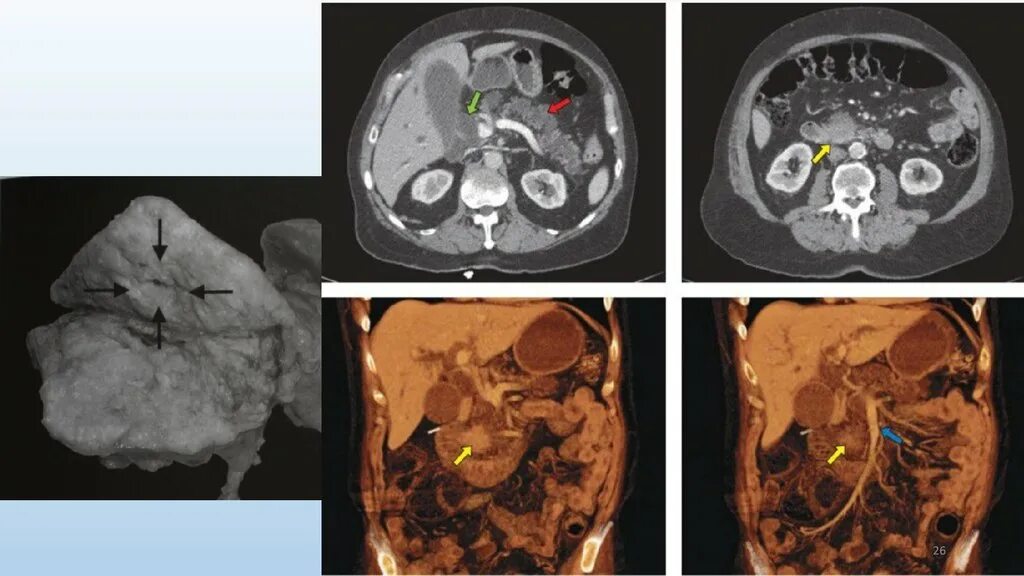

Метастазы в поджелудочную железу прогноз